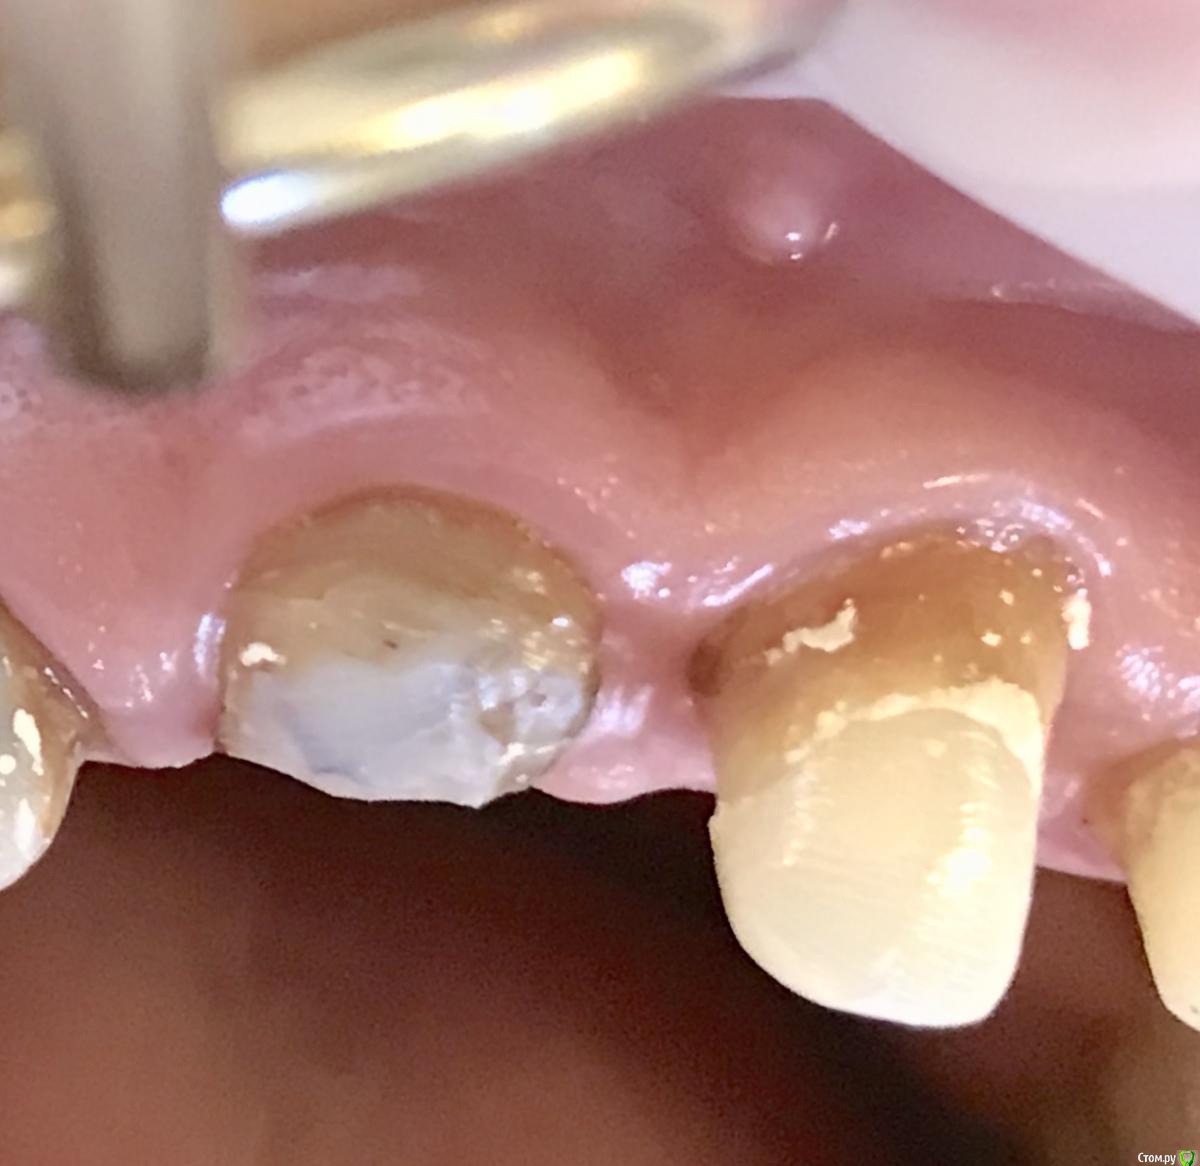

Shakirbura Опубликовано 21 августа, 2018 Поделиться Опубликовано 21 августа, 2018 Прошло 3 месяца. Фото "шайбы" выкладывал ранее. 2 Ссылка на комментарий

Shakirbura Опубликовано 22 августа, 2018 Поделиться Опубликовано 22 августа, 2018 тут изначально хорошая вестибулярная выстилка, думаю хорошо было бы и без шайбы, а когда тонкая, она уходит у меня почему то и с шайбой и без шайбы... Хорошая то да, но 2мм потеряли. Ссылка на комментарий